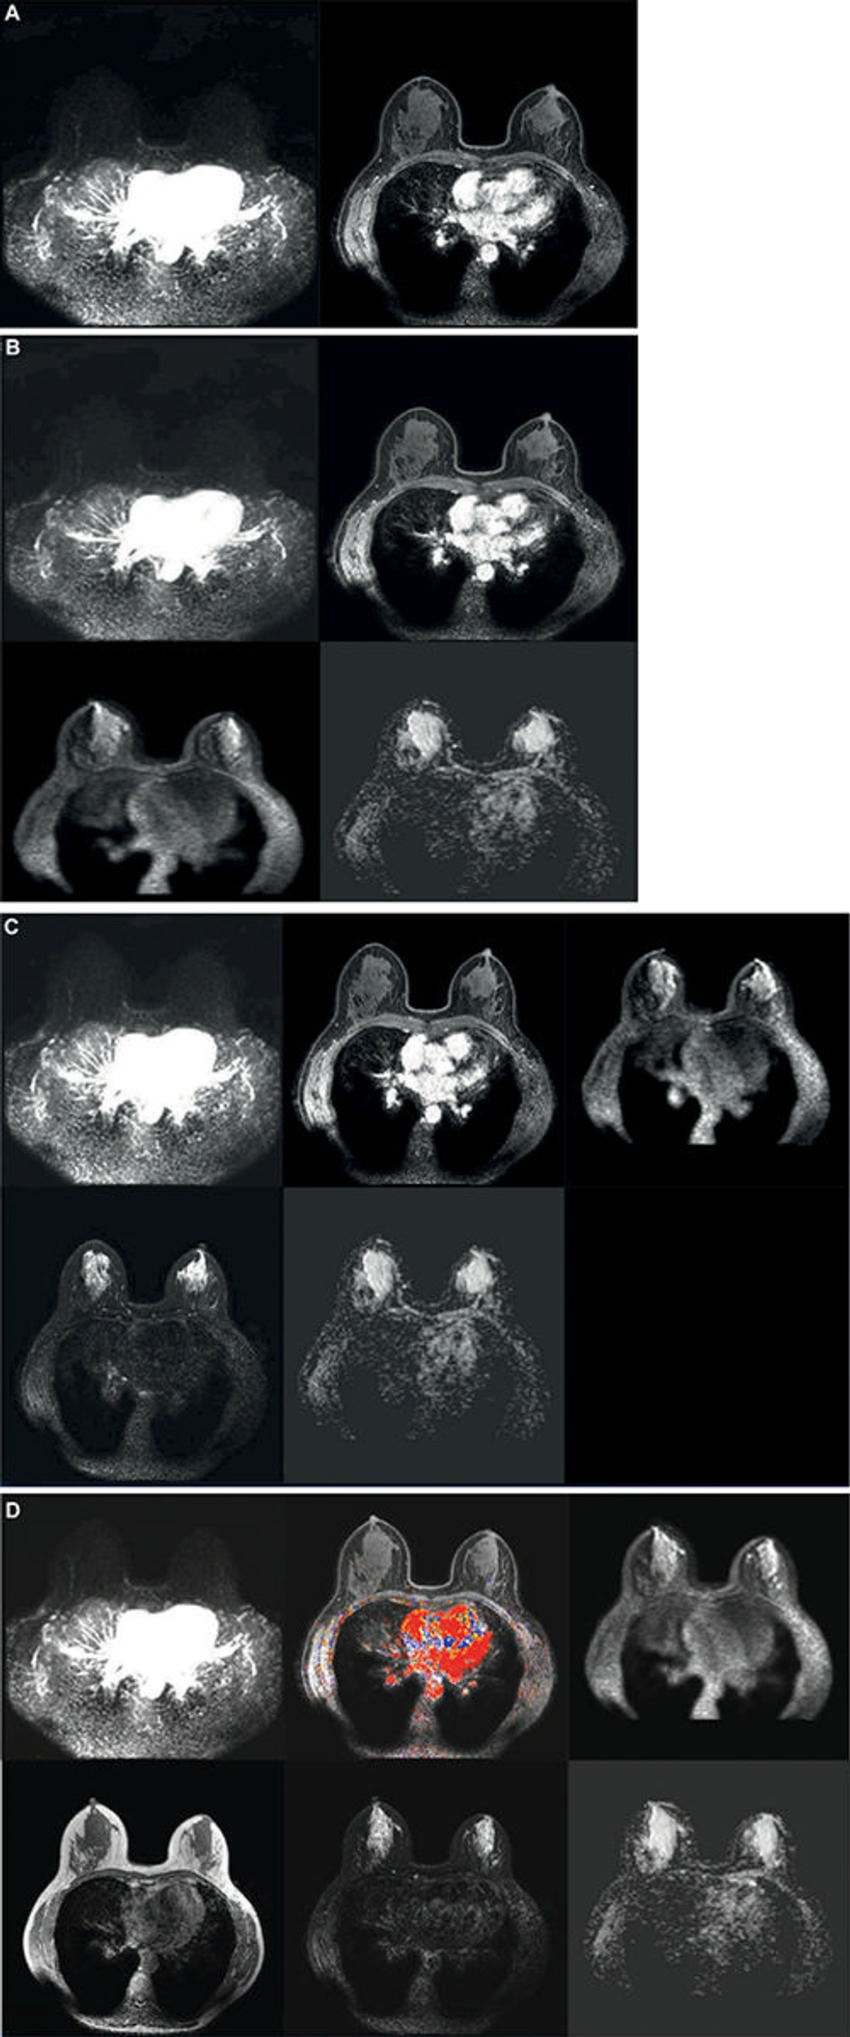

Figure 1. Axial images show the incremental steps 1–4. (A) Step 1: The first step consisted of the dual high-temporal low-spatial and low-temporal high-spatial dynamic T1 series, from before contrast material injection to 120 seconds after contrast injection only. (B) Step 2: The second step added diffusion-weighted images to the series available from step 1. (C) Step 3: The third step added T2-weighted images to the series available from steps 1 and 2. (D) Step 4: The fourth and final step added non–fat-saturated T1-weighted precontrast images, all remaining dynamic phases acquired after the first 120 seconds after contrast administration, and enhancement curve kinetics to the series available from steps 1, 2, and 3. This final step is the full multiparametric breast MRI protocol that was used in the Dense Tissue and Early Breast Neoplasm Screening (DENSE) trial. The curve kinetics overlay is a colormap showing the standard three types of delayed curve kinetics: type-I kinetics, persistent increase (blue); type-II kinetics, plateau (yellow); and type-III kinetics, washout (red).